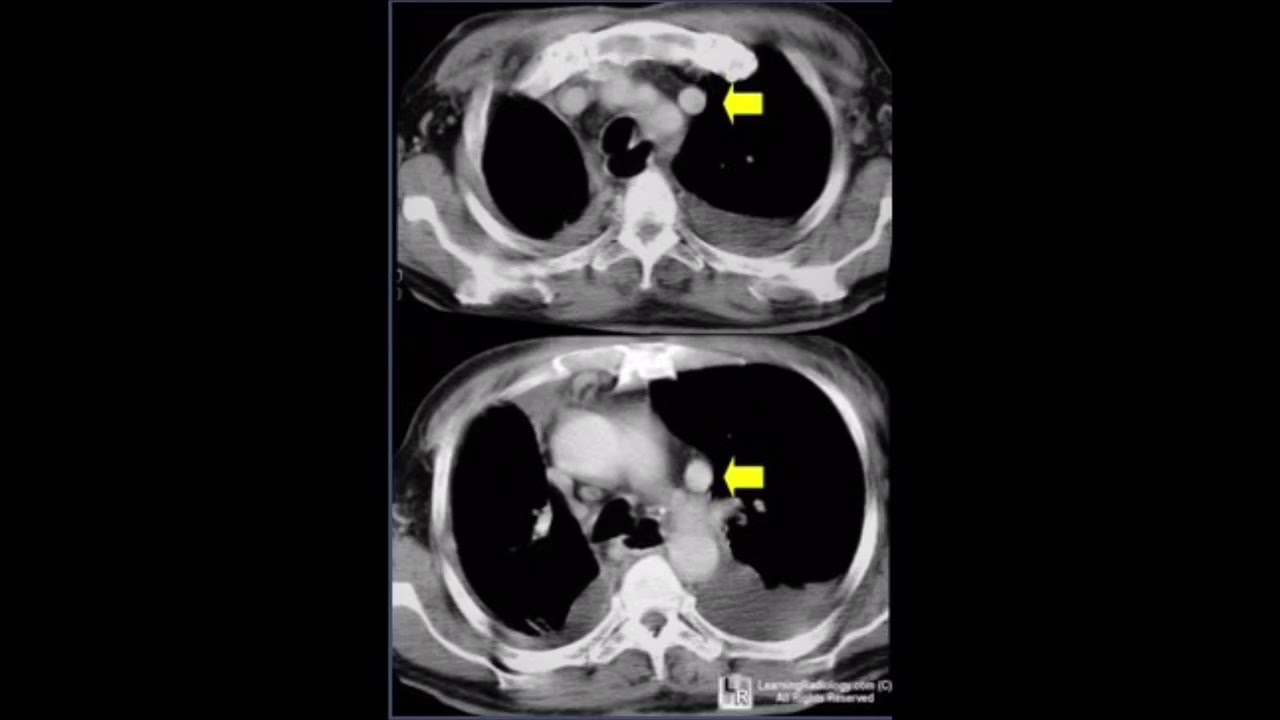

Persistent Left Superior Vena Cava - YouTube

If you are trying to find video details pertaining to Persistent Left Superior Vena Cava - YouTube search phrases, you have involved the appropriate blog site. Our blog has a number of collections of video clips from the very best resources appropriate to what you are trying to find such as Persistent left superior vena cava 2 - YouTube, Persistent Left Superior Vena Cava - YouTube and also absent right and persistent left superior vena cava (prenatal diagnosis.

Play

Next is a video clip regarding Persistent Left Superior Vena Cava - YouTube which is currently trending and also is being looked for by several netizens, you can play it directly on this web page for ideas or maybe download videos to be utilized as video collections on your device.